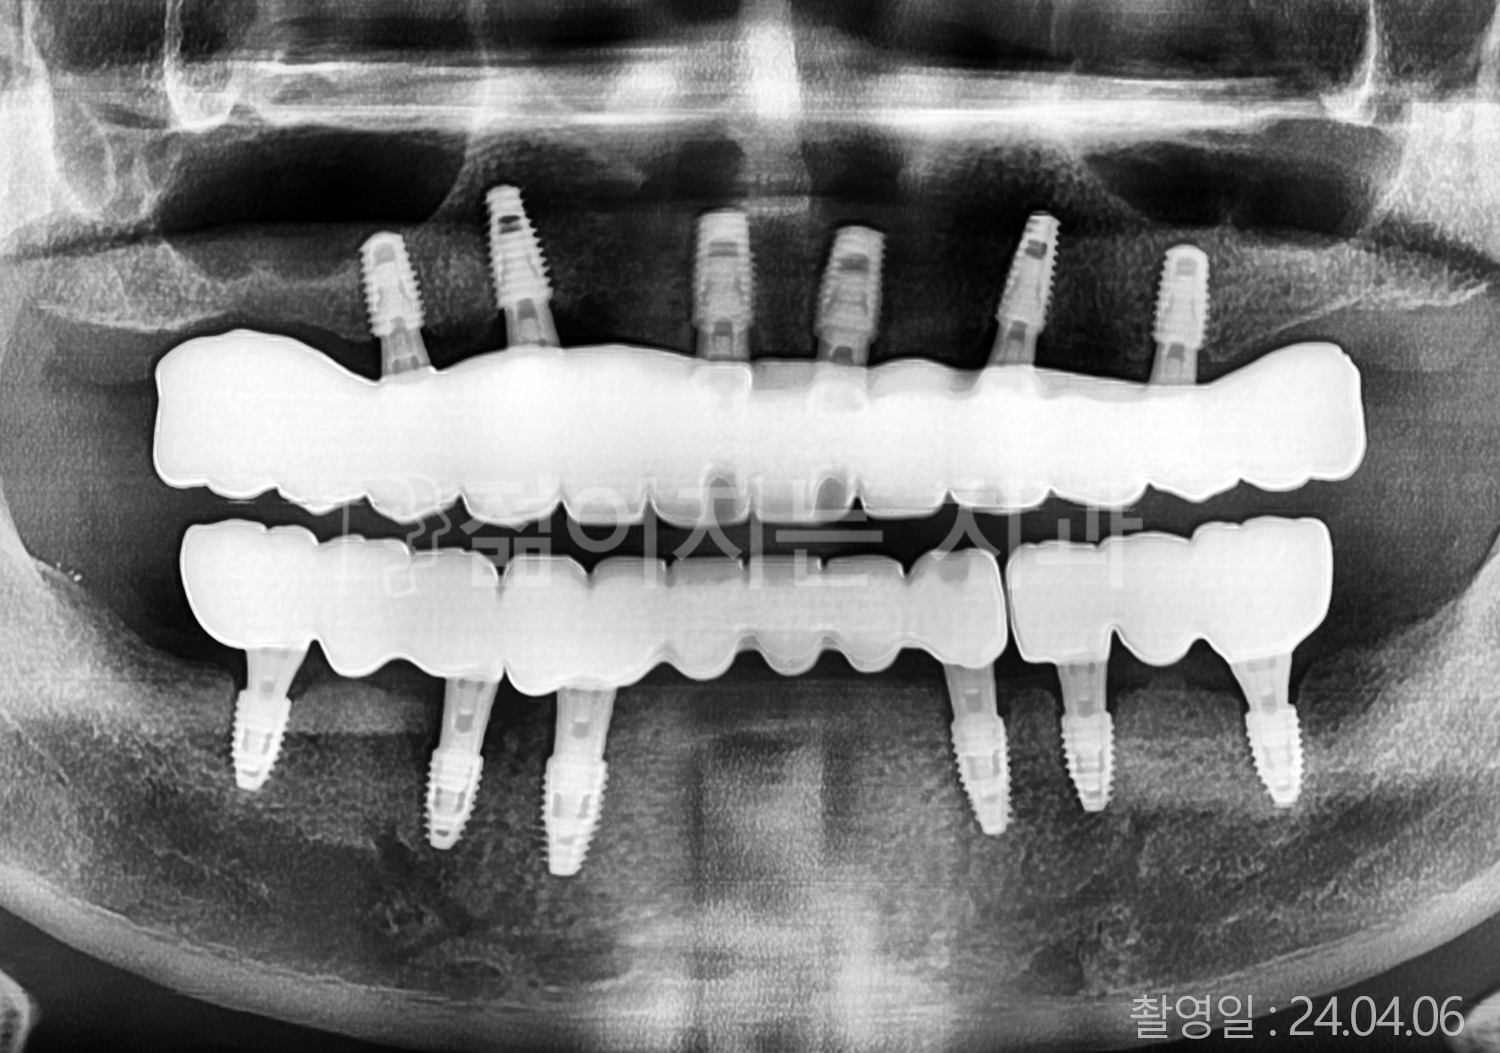

• 50대 전체치아 10개 이상 임플란트

• 50대 고혈압, 고지혈증 전체치아 10개 이상 임플란트